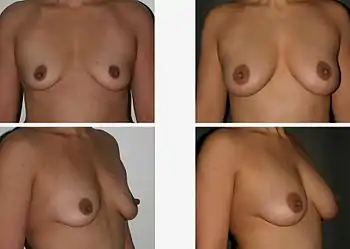

Repair and revision surgeries

The technique of autologous fat-graft injection to the breast is applied for the correction of breast asymmetry or deformities, for post-mastectomy breast reconstruction (as a primary and as an adjunct technique), for the improvement of soft-tissue coverage of breast implants, and for the aesthetic enhancement of the bust. The careful harvesting and centrifugal refinement of the mature adipocyte tissue (injected in small aliquots) allows the transplanted fat tissue to remain viable in the breast, where it provides the anatomical structure and the hemispheric contour that cannot be achieved solely with breast implants or with corrective plastic surgery.

In fat-graft breast augmentation procedures, there is the risk that the adipocyte tissue grafted to the breast(s) can undergo necrosis, metastatic calcification, develop cysts, and agglomerate into palpable lumps. Although the cause of metastatic calcification is unknown, the post-procedure biological changes occurred to the fat-graft tissue resemble the tissue changes usual to breast surgery procedures such as reduction mammoplasty. The French study Radiological Evaluation of Breasts Reconstructed with Lipo-modeling (2005) indicates the therapeutic efficacy of fat-graft breast reconstruction in the treatment of radiation therapy damage to the chest, the incidental reduction of capsular contracture, and the improved soft-tissue coverage of breast implants.[116][117][118][119][120][121]

The study Fat Grafting to the Breast Revisited: Safety and Efficacy (2007) reported successful transfers of body fat to the breast, and proposed the fat-graft injection technique as an alternative (i.e., non-implant) augmentation mammoplasty procedure instead of the surgical procedures usual for effecting breast augmentation, breast defect correction, and breast reconstruction.

Structural fat-grafting was performed either to one breast or to both breasts of the 17 women; the age range of the women was 25–55 years; the mean age was 38.2 years; the average volume of a tissue-graft was 278.6 cm3 of fat per operation, per breast.

The pre-procedure mammograms were negative for malignant neoplasms. In the 17-patient cohort, it was noted that two women developed breast cancer (diagnosed by mammogram) post-procedure: one at 12 months, and the other at 92 months.[122] Further, the study Cell-assisted Lipotransfer for Cosmetic Breast Augmentation: Supportive Use of Adipose-Derived Stem/Stromal Cells (2007), an approximately 40-woman cohort indicated that the inclusion of adipose stem cells in the grafts of adipocyte fat increased the rate of corrective success of the autologous fat-grafting procedure.[123]